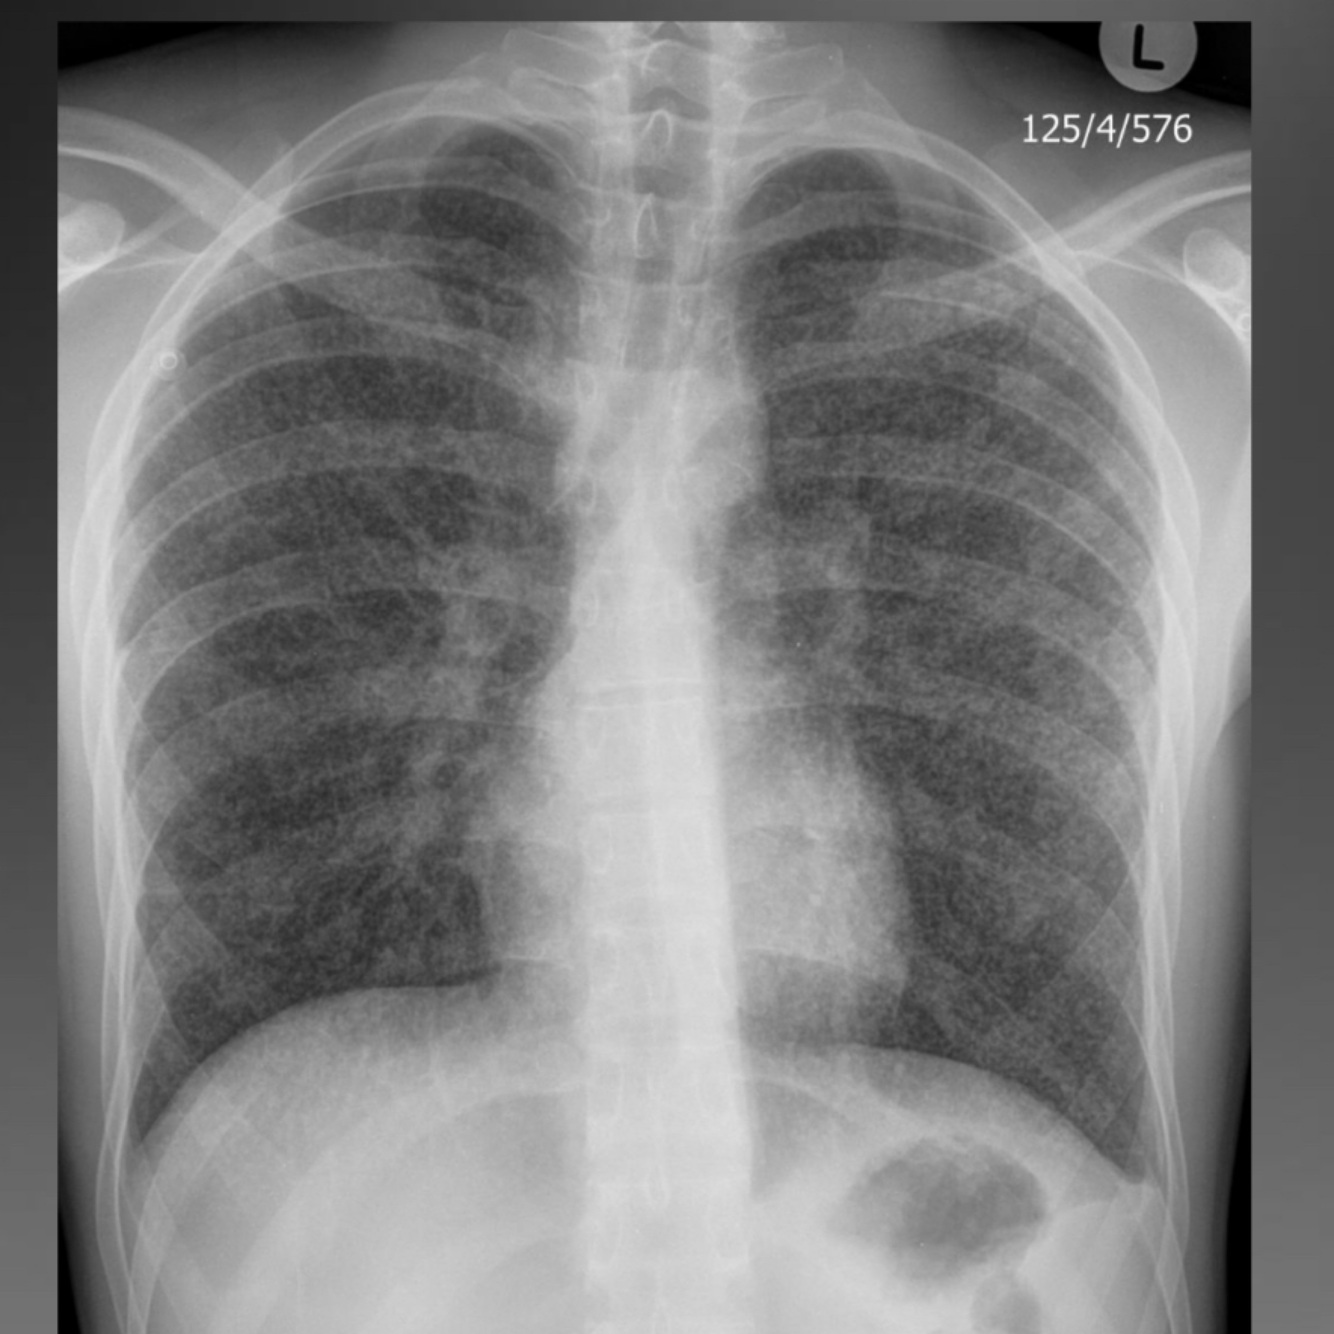

Suspected tb

A

Hallmarks of active disease on CXR

Primary:

lymphadenopathy

consolidation

nodules

pleural effusion

miliary nodules

Primary infection

1st exposure infection

Ghon focus: localized

Ranke complex: local infection with nodal spread

Asymptomatic / symptomatic

CXR: consolidation, atelectasis in children, LAD, pleural

effusion

Consolidation and lymphadenopathy